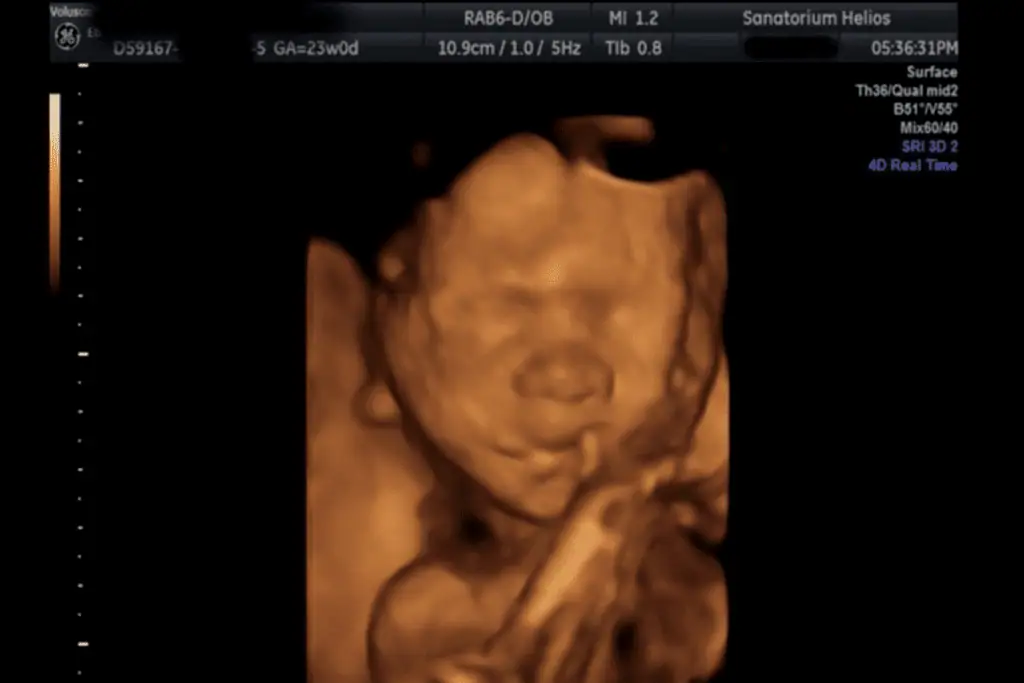

3D, 4D Ultrazvuk

Jako třetí pracoviště v České republice a jako první privátní zařízení mělo Sanatorium Helios k dispozici trojrozměrný ultrazvuk GE Voluson 730. Nově je možné také vyšetření na nejmodernějším přístroji Voluson E10.

Nejvhodnější je záznam plodu mezi 20. – 26. týdnem těhotenství.

Kvalita záznamu na 3D/4D je vždy ovlivněna polohou plodu a polohou placenty, množstvím plodové vody a konstitucí pacientky. Pokud je např. plod přitisknut k děložní stěně nebo k placentě ev. má před obličejem ruce nebo nohy, je zobrazení na 3D velmi nepřesné a mnohdy nejdou kontury tváře vůbec zobrazit.

Ze 3D a 4D ultrazvukového vyšetření lze pořídit fotografii či DVD záznam.

Tyto fotografie jsou pořízené přístrojem Voluson 730